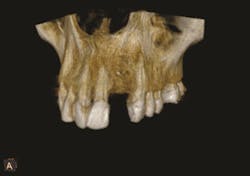

3. Then, using interactive software for treatment support, the data from the CBCT scan and digital impression are merged together. Figures 1-3.

What is the point of obtaining both extraoral and intraoral images? While the clinician can gain valuable insight about the mandible or maxilla, CBCT does not provide enough information about the surface detail of the teeth or soft tissues.2 When CBCT information is combined with the digital impression in the interactive treatment software, the doctor’s diagnostic capabilities are greatly enhanced, and, consequently, so is treatment planning.